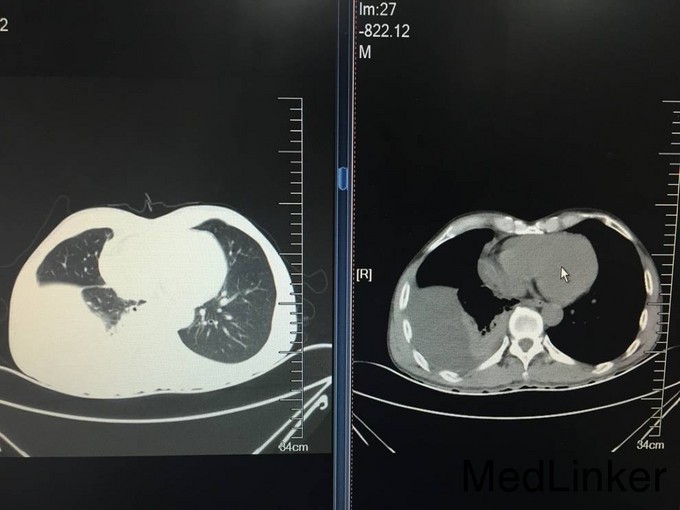

患者老年男性,以“胸闷气短8天”为主诉入院。 患者8天前无明显诱因出现胸闷气短,活动时加重,伴间断咳嗽咳痰,痰为白痰,伴间断发热,体温最高38.8℃,无发冷及寒战,夜间盗汗明显。自行口服阿莫西林、阿奇霉素等药物,症状未见明显缓解,遂就诊于沈阳市第五医院。行肺CT检查,提示:右侧胸腔包裹下积液并左肺下叶膨胀不全,建议进一步检查及复查。左肺上叶陈旧病变。血常规未提示白细胞及中性粒细胞百分比水平升高。患者病来无头晕头痛,无胸痛咯血,无恶心呕吐。食睡眠差,大小便如常,体重未见明显减轻

查体:T:37.5℃,BP:105/80mmHg,P:80次/分,R:18次/分;神清语明,步入病房,查体合作,睑结膜无苍白,口唇无发绀,浅表淋巴结未触及肿大,咽无充血,扁桃体未见肿大,颈软,气管居中,颈静脉无怒张。双肺听诊呼吸音粗,右侧下肺野呼吸音消失,双肺未闻及明显干湿啰音。心界不大,心音钝,节律齐,心率80次/分,各瓣膜听诊区未闻及杂音。全腹软,无压痛,无反跳痛及肌紧张,肝脾肋下未触及,肝肾区无叩痛,无杵状指,双下肢无水肿。 CRP:137.0mg/L。血常规:白细胞计数 6.7*10^9/L,中性粒细胞百分比 70.8%,血红蛋白115g/L,血小板计数 356*10^9/L。降钙素原检测:降钙素原 0.065ng/mL。军团菌、结核抗体、支原体抗体、衣原体抗体均阴性。凝血五项:凝血酶原时间 13.80秒,纤维蛋白原含量 5.84g/L,D-dimer 1101ug/L。一般细菌涂片检查:细菌涂片结果。呼吸道正常菌群。1-3-β-D葡聚糖定量检测:132.8。甲功系列、肺癌系列无异常。生化:总蛋白 54.1g/L,白蛋白 32.5g/L,前白蛋白 0.07g/L,血糖5.01mmol/L,痰结核培养均阴性,患者未成功留取痰结核菌涂片化验。患者入院第二日请介入科会诊,行右侧胸腔穿刺引流术,留置右侧胸腔引流管一枚,引流淡黄色透明液体,引流第一天引流液体800ml,将引流管夹闭,引流液留取化验。胸水化验回报:LDH:乳酸脱氢酶 583;胸腹水常规检查:李凡他试验 阳性(+);白细胞计数 2.89210^9/L;单个核细胞百分比 96.2%;体液ADA:腺苷脱氨酶 61U/L;细菌培养:培养结果 未见细菌生长。胸水结核菌涂片及结核菌培养均阴性。血T-SPOT:混合淋巴细胞培养 50细胞数;A抗原刺激+γ-干扰素 11SFCs/2.5*105PBMC;B抗原刺激+γ-干扰素 6SFCs/2.5*105PBMC。患者胸水病理检查未查见肿瘤细胞。目前患者化验结果提示胸水ADA水平较高,胸水李凡他试验阳性,胸水淋巴细胞比例较高,考虑患者结核性胸水可能性大。患者近日流量管未见引流液流出,复查肺CT,结果:右肺上叶结节,性质待定。右侧胸腔积液,叶间包裹性积液,右肺下叶部分受压不张。左肺上叶钙化灶,双肺散在慢性炎症。心包积液。右侧心膈角淋巴结稍增大。左肾低密度影,必要时进一步检查。请胸科医院会诊,考虑患者结核胸膜炎可能性大,建议转入胸科医院行诊断性抗结核治疗,同时反复胸水病理检查除外恶性。

患者有胸水,有结节,注意鉴别结合和肿瘤,必要时活检病理检查。